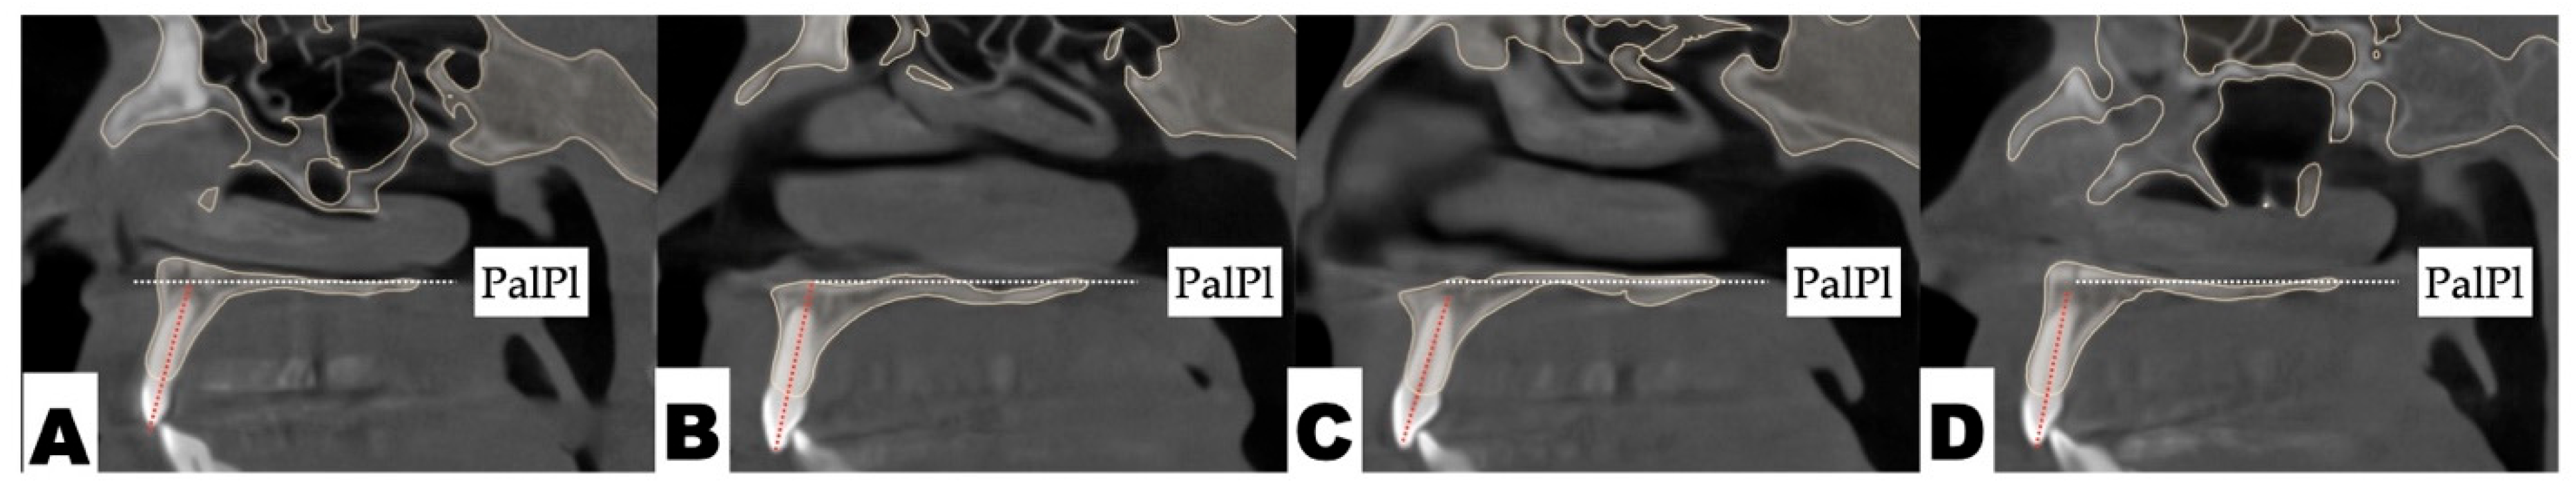

2.3.1. Surgical Protocol

2.3.2. Design of 3D Surgical Guide

2.3.3. Osteotomy Planning and Appliance Design